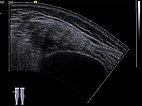

Ultrasound image (automatically assembled 2D image) before sclerotherapy. The cavities of the venous malformation are initially hypoechoic to echo-free. These cavities will be occluded by the inflammation induced by the sclerotherapy.

Ultrasound image (automatically assembled 2D image) after sclerotherapy. The hypoechoic cavities of the venous malformation are now occluded by the inflammation induced by sclerotherapy. The image now appears more homogeneous and echogenic on ultrasound. After occlusion of the cavities, painful thrombophlebitis can no longer occur.